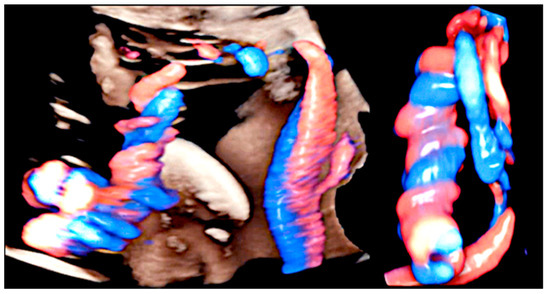

3.1. Cord Coiling